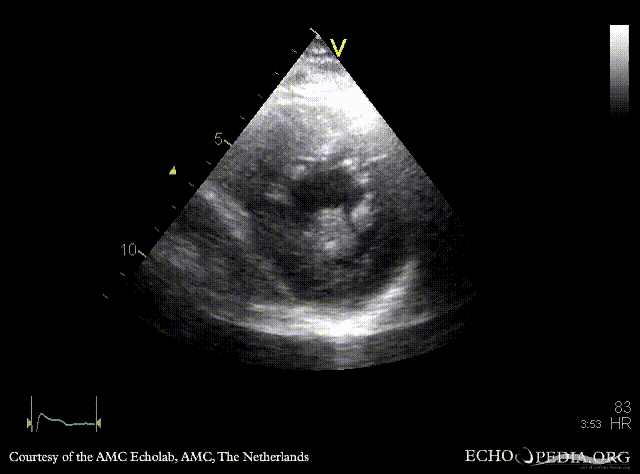

Giant myxoma in left atrium

PLAX: giant mobile myxoma in left atrium